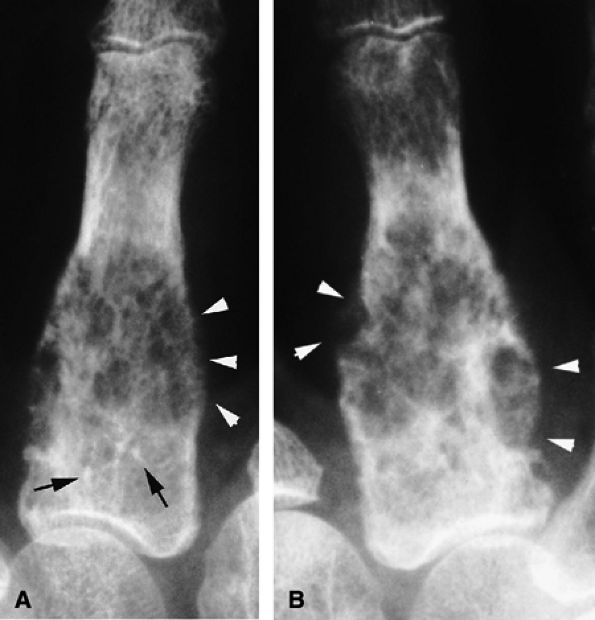

seen with synovial sarcomas. Bone and joint invasion is possible.168 Ultrasonography shows a nonspecific solid mass with a variable color Doppler signal. MR images are specific, depicting a well-defined mass with hemosiderin deposits. Typical signal void artifacts are seen on all sequences, particularly on gradient-echo images, and a more heterogeneous and predominantly low signal is found on T2-weighted images.162,166,169 The lesion typically enhances after intravenous injection of gadolinium (Fig. 11.74). The tendon sheath of the flexor digitorum tendons is usually partially or totally enveloped; the extensor tendons are less commonly involved. Some lesions may be more aggressive, and diffuse lesions are seen in multiple locations with invasion of both the flexor and extensor tendons (Fig. 11.75).170

FIGURE 11.73 ● Giant cell tumor of the tendon sheath. Lateral view radiograph shows a large mass of the palmar soft tissue (asterisk) and bone pressure erosion (arrows).

FIGURE 11.74 ● Giant cell tumor of the tendon sheath. Sagittal T2-weighted image (A) and post-contrast T1-weighted image (B) show a palmar mass (arrows) close to the sheath of the flexor tendons with predominant low signal (arrowhead) on the T2-weighted image and strong enhancement following contrast administration.

FIGURE 11.75 ● Aggressive giant cell tumor of the tendon sheath. Sagittal post-contrast 3D gradient-echo (A) and axial T1-weighted (B) images depicting a multinodular tumor invading the flexor and extensor tendons as well as the head of the phalanx (arrow).